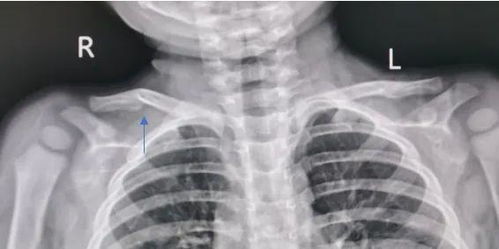

第一步,先搞清楚:锁骨骨折,一定是“轻伤”吗?

这还真不一定!咱们老百姓嘴里的“轻伤”和法律上的“轻伤”完全是两码事,法律上的伤情鉴定,那是非常严格和专业的,有专门的《人体损伤程度鉴定标准》,锁骨骨折,根据骨折的部位、程度(比如有没有移位、粉碎性骨折、有没有损伤到周围神经血管等),鉴定结果可能是“轻微伤”,也可能是“轻伤二级”或者“轻伤一级”,严重的甚至可能达到“重伤”。